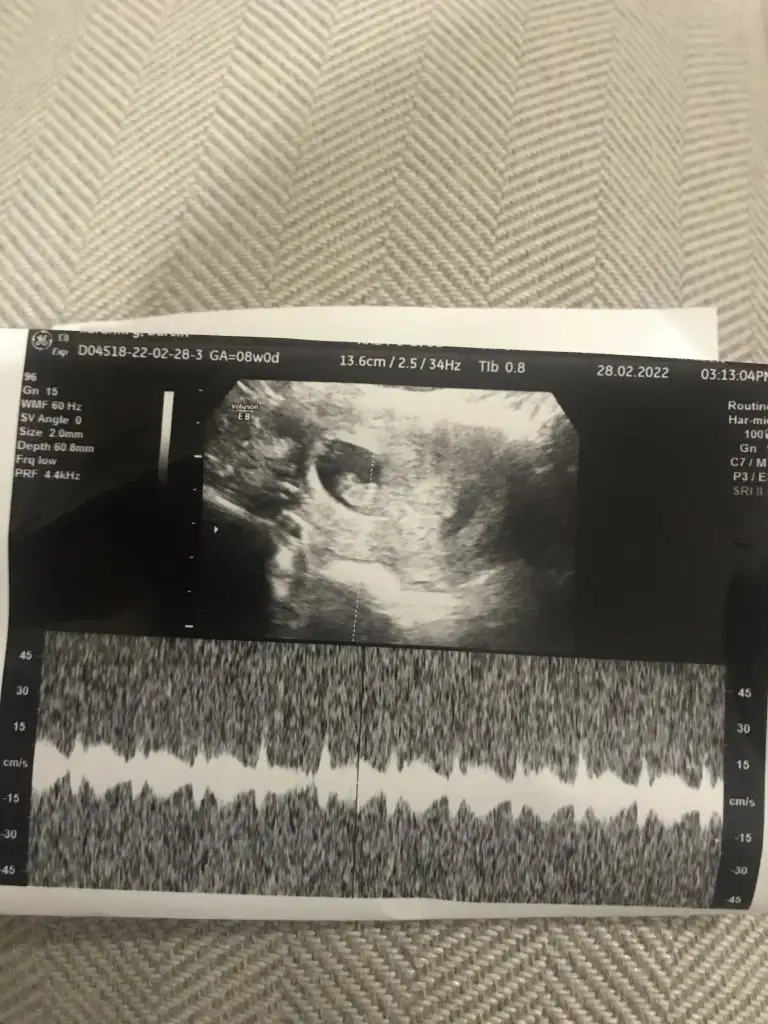

Merhabalar vajinal ultrasondan 7+5 de cekildi cinsiyeti sizce nedir tahminde bulunur musunuzSelam Kızlarbir çok kişi gruplardan beni bilir. Yine yetiştim imdatlara

erkek gibi kuzumMerhabalar vajinal ultrasondan 7+5 de cekildi cinsiyeti sizce nedir tahminde bulunur musunuz